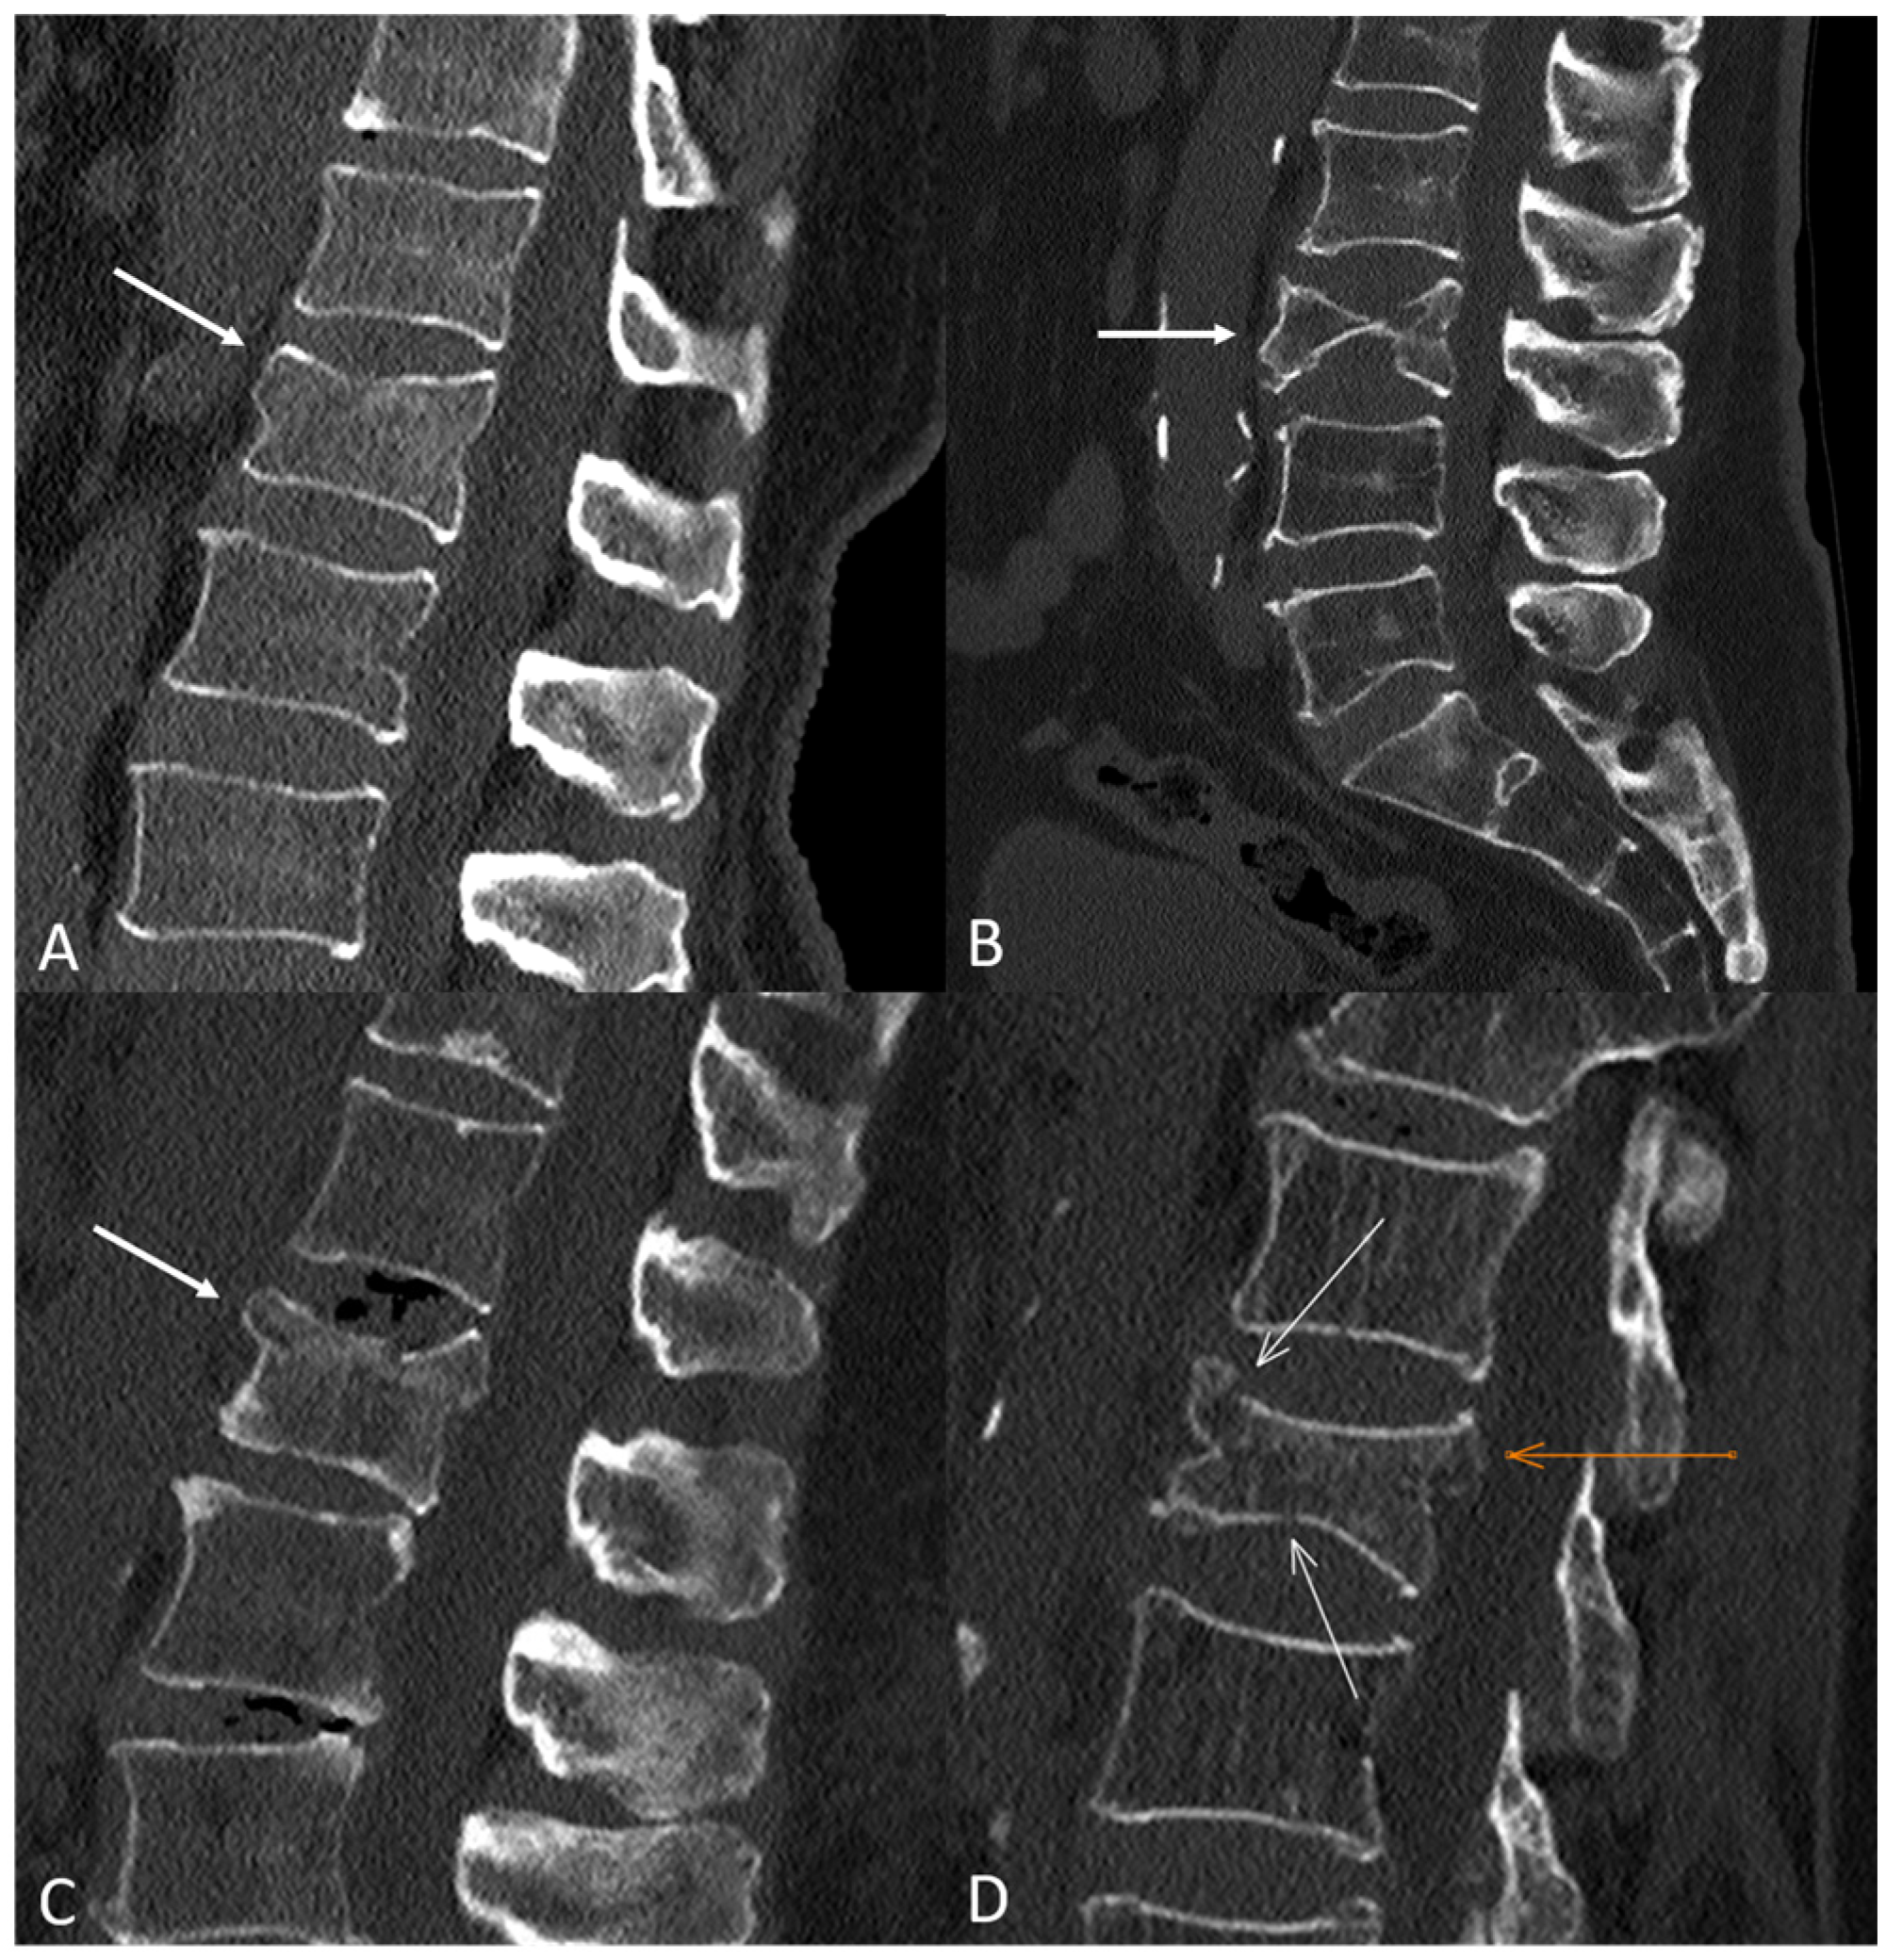

Bivariate analyses showed significant associations between all classification systems, except Genant et al.’s quantitative, and vertebral collapse. The highest rate of collapse among all classifications was observed in the A4 category of the AO Spine, with 24 out of 28 (85.7%) OVFs developing vertebral collapse on follow-up. Figure 1 shows illustrative examples of A1-A4 AO Spine classification fractures, and Figure 2 summarizes the incidence of collapse in these fractures. Table 1 shows the incidence of the different types of OVFs and the results of bivariate analyses.

Figure 1. Illustrative examples of osteoporotic vertebral fractures in our sample based on the AO Spine classification system. (A) A1-type fracture of L1 (white arrow). Note the subtle loss of vertebral height and the trabecular fracture line below the superior endplate, as well as the absence of posterior wall displacement. (B) A2-type fracture of L3 (white arrow) with a typical pincer-like morphology, involving the central part of the vertebral body. (C) A3-type fracture of L1 (white arrow) involving the superior endplate, with mild displacement of the posterosuperior wall to the spinal canal. (D) A4-type fracture of L2, with involvement of the superior and inferior endplates (white arrows) and displacement of the posterosuperior wall to the spinal canal (orange arrow).